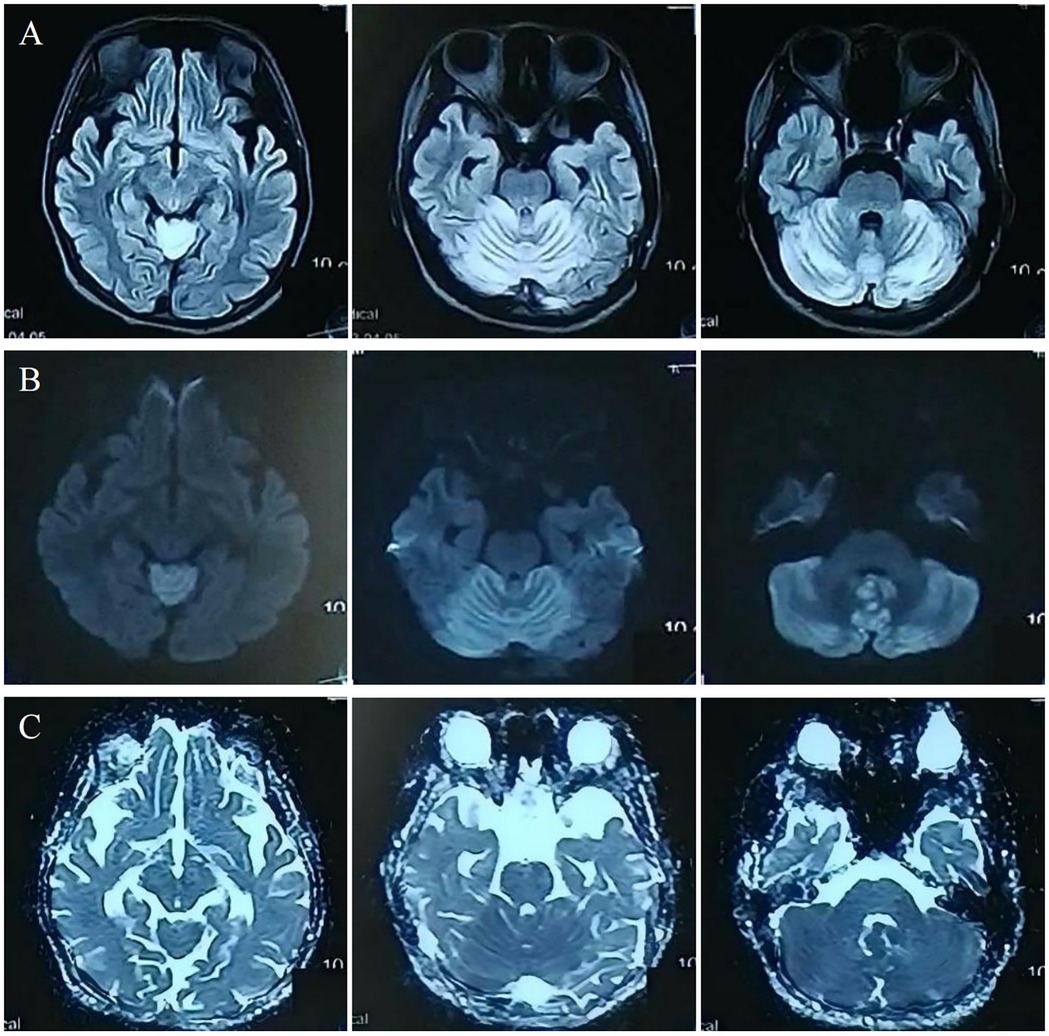

Investigations revealed severe anemia (hemoglobin 93 g/L, ref: 114–154 g/L) and hyperhomocysteinemia (210 µmol/L, ref: ≤15 µmol/L). Laboratory investigations also revealed an elevated blood propionylcarnitine/acetylcarnitine ratio (C3/C2: 0.21; ref: 0.02–0.20) and significantly increased urinary methylmalonic acid (17.5; ref: 0.0–4.0) with mild methylcitric acid elevation (0.8; ref: 0.0–0.7) on tandem mass spectrometry and organic acid analyses. Cranial MRI showed bilateral cerebellar hyperintensities on MRI DWI/FLAIR (Figure 1). Whole-exome sequencing identified compound heterozygous MMACHC mutations (c.80A > G, c.482G > A), confirming a diagnosis of cblC-type MMA-HC.

The symptoms resolved gradually following a one-month course of treatment, which included intramuscular injection of mecobalamin (500 μg once daily), as well as oral administration of vitamin B6 (10 mg three times daily), folic acid (5 mg once daily), and idebenone (30 mg three times daily). Follow-up 3.0 T MRI showed significant resolution of the cerebellar lesions on DWI and FLAIR (Figure 2A–D). Crucially, 7.0 T and 3.0 T MRI SWI revealed multiple punctate microhemorrhages in the cerebellar vermis (Figure 2E–H). The long-term treatment plan for the patient consists of lifelong medication including intramuscular injection of mecobalamin 500 μg once daily—to be reduced to once weekly after homocysteine levels stabilize—along with oral folic acid 5 mg once daily, and oral vitamin B6 10 mg three times per day. In addition, regular monitoring of plasma homocysteine, folate levels, and renal function is recommended, with dosage adjustments made based on the results.

Figure 2. Post-treatment: cerebellar lesion resolution [(A–D), 3.0 T]; vermian microhemorrhages on 7.0 T SWI (E,F) and 3.0 T SWI (G,H).